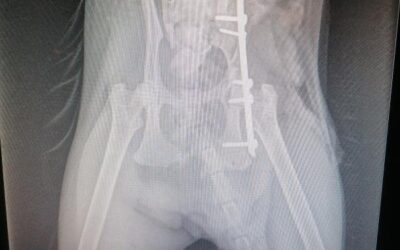

L’orthopédie

C’est une spécialité chirurgicale pratiquée par un chirurgien orthopédiste, donc un spécialiste. fracture transversale 1/4 distal du tibia A la Clinique Vétérinaire du Mail près de Lons, nous opérons donc les fractures, articulations, muscles, tendons et...